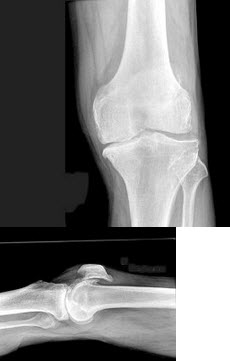

男,76岁,长久站立时左膝关节疼痛,可扪及捏发音,结合图像,最可能的诊断是( )

A、退行性骨关节病

B、畸形性骨炎

C、神经性关节病

D、创伤性关节炎

E、肥大性骨关节病

男,76岁,左膝关节长久站立时疼痛,可捫及捏发音,请结合图像,选出最可能的诊断